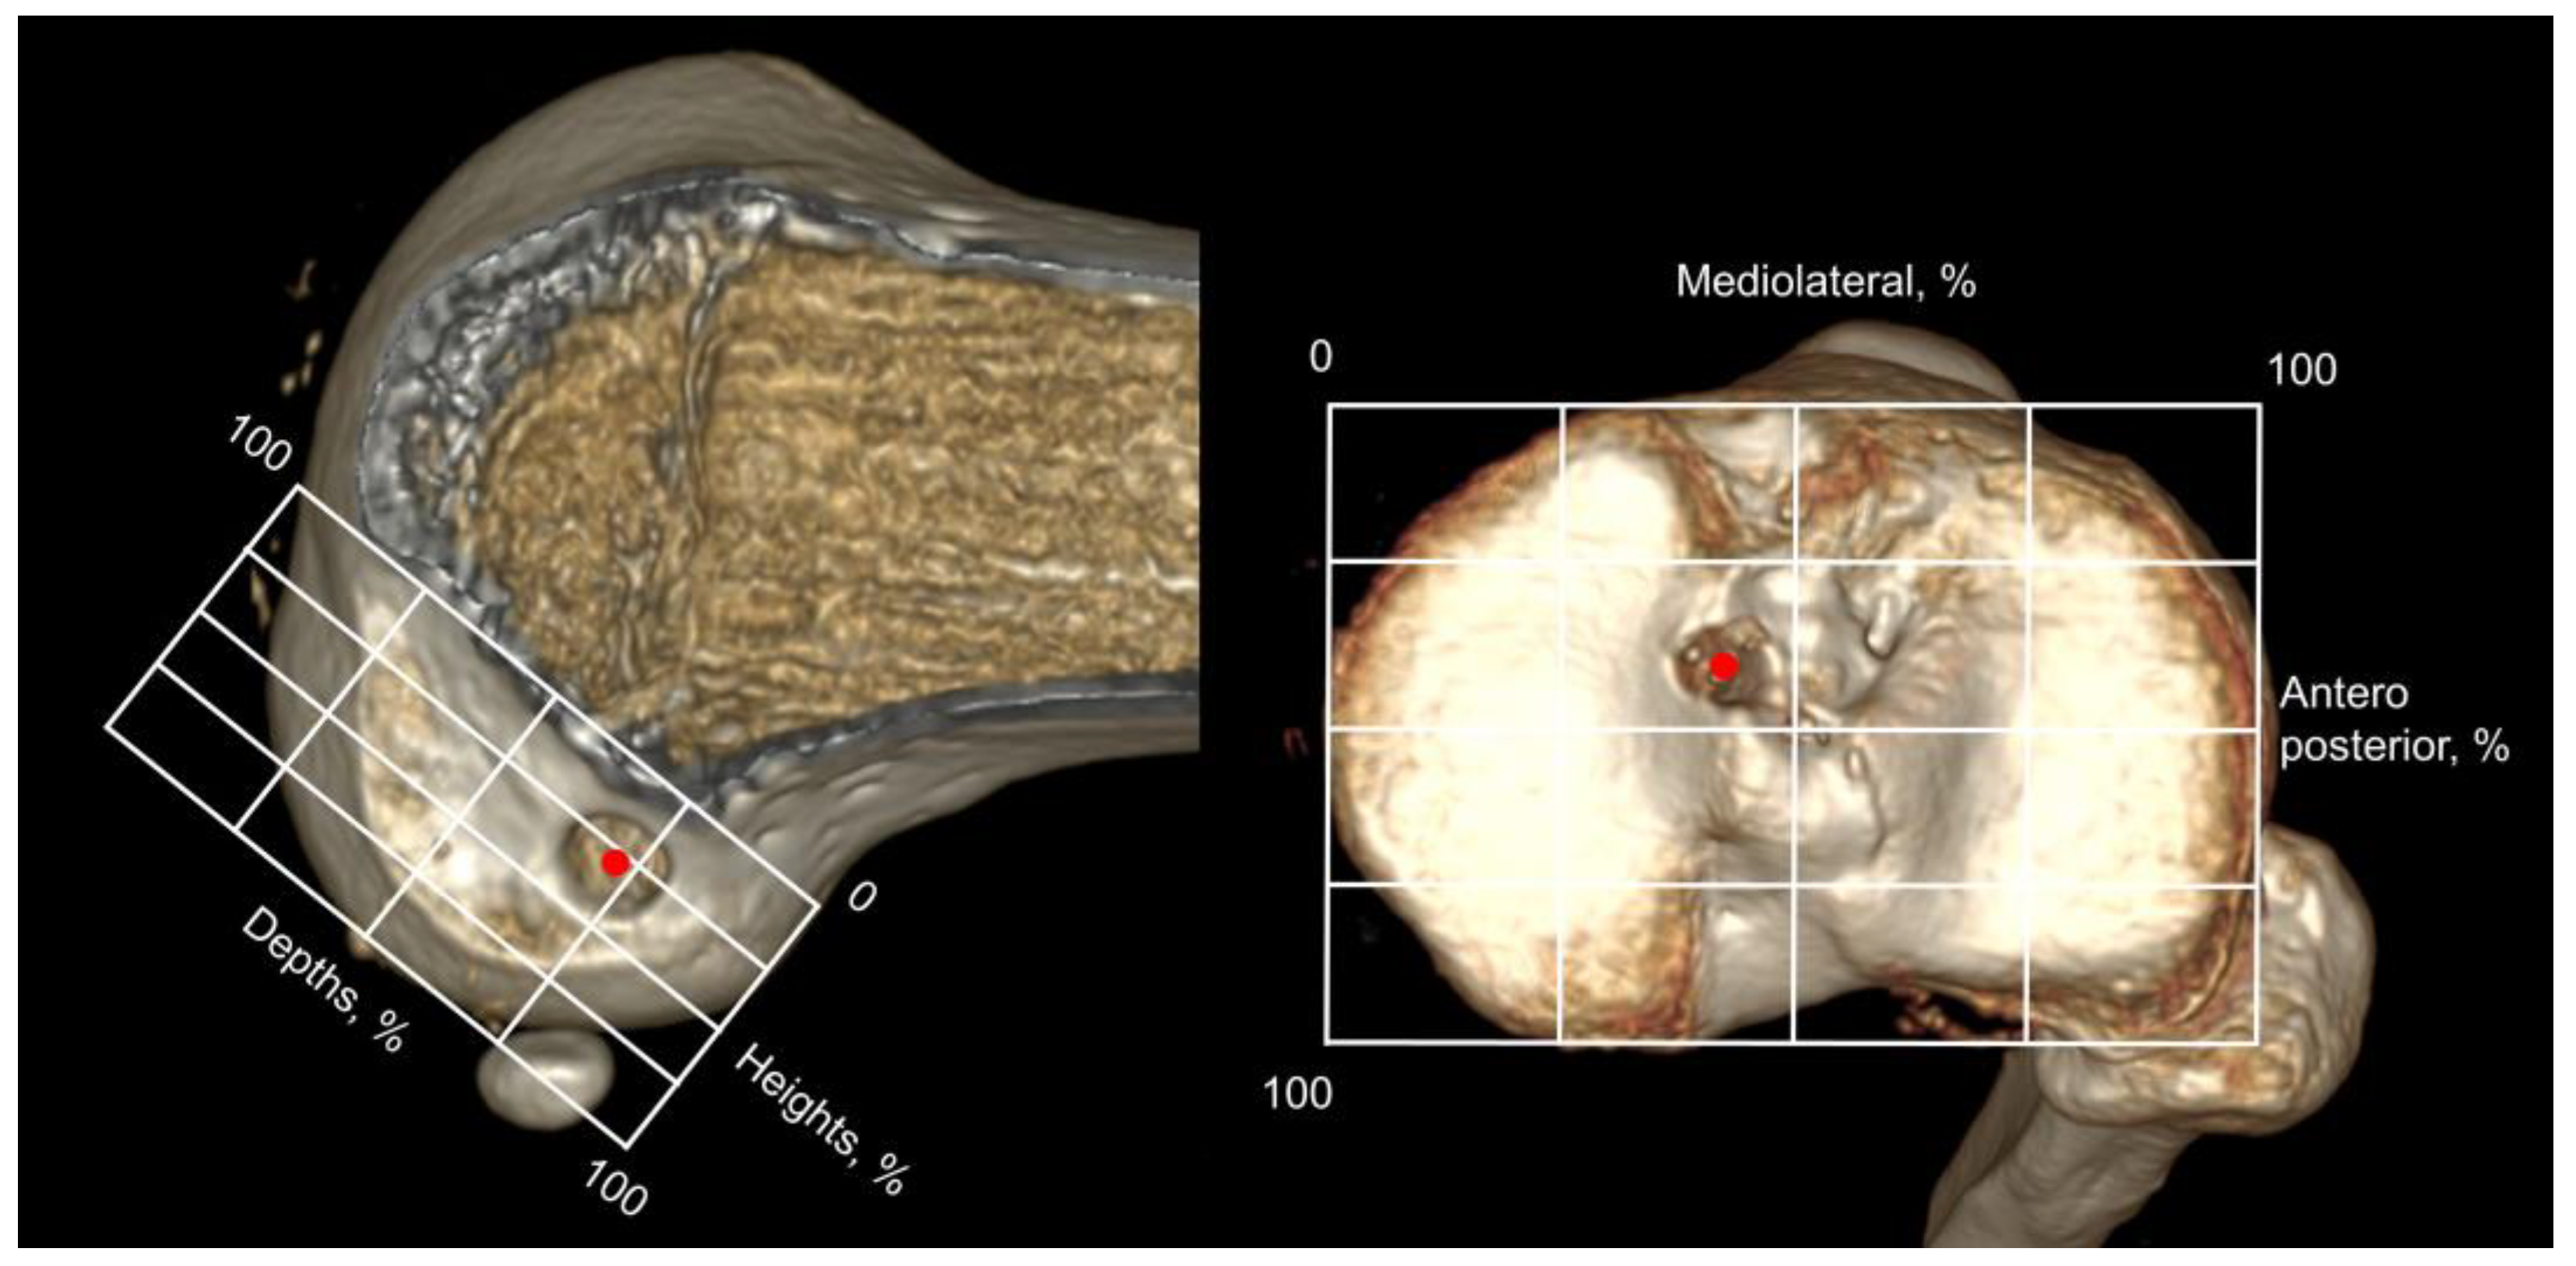

Computed tomography (CT) was performed 3 days postoperatively. Three-dimensional CT images were used to measure the femoral and tibial tunnel positions. The center of the femoral and tibial tunnel apertures was measured on the standardizeds grid system as described previously [20]. In terms of the femoral tunnel, the higher limit of the grid was located on the femoral notch roof, and the anterior, posterior, distal, and proximal sides of the grid were located on the articular cartilage margin. The height and depth of the femoral tunnel were measured. With respect to the tibial center, a rectangular grid was located at each end edge of the tibial plateau. The AP and mediolateral (ML) tibial tunnel positions were then calculated (Figure 5).

Figure 5.

The center of the femoral and tibial tunnel (red dots) was calculated on 3-dimensional CT with the quadrant method. The height and depths of femoral tunnel position and anteroposterior and mediolateral tibial tunnel position were measured.